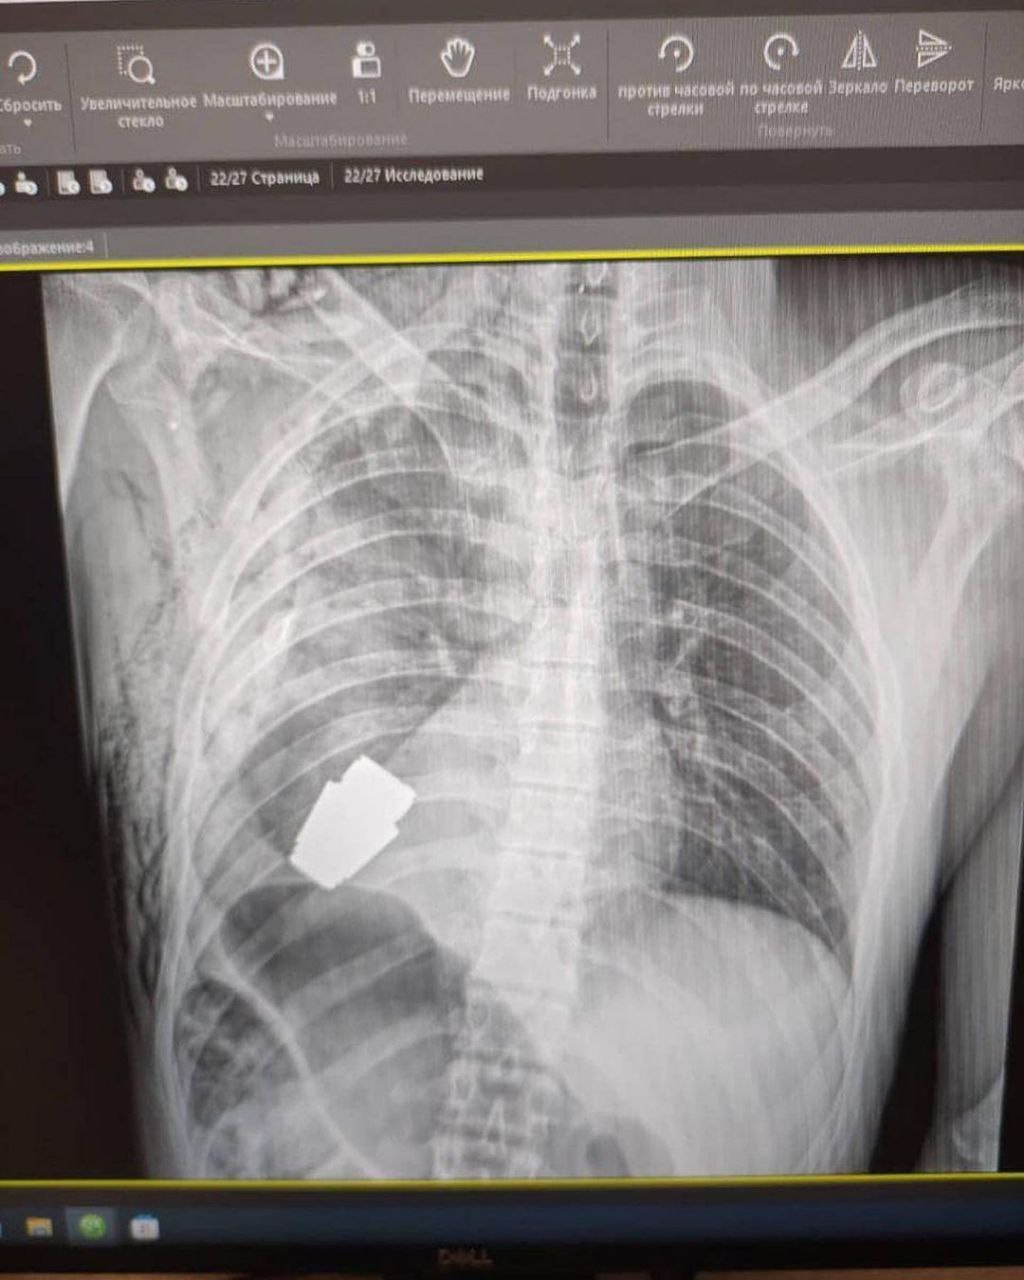

Details about how the child is feeling now, see in the YouTube videoThe child who was injured during the shelling of Shevchenkove may need psychological help A 10-year-old child who was injured during a rocket attack on the market in Shevchenkove on January 9 may need the help of a psychologist. This opinion was expressed in a comment to Suspilne Kharkiv by Yevhen Strelets, who is the deputy director general for surgical care of the medical institution in which the child is staying. Subscribe and press 🔔 to receive notifications about new videos and broadcasts